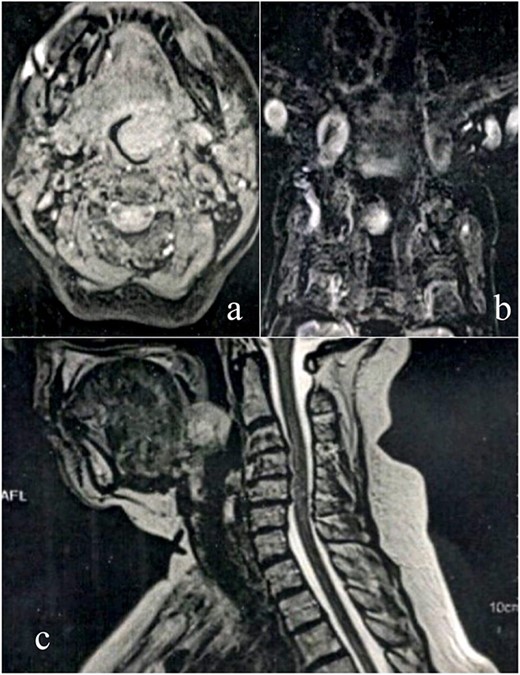

A female patient, 72 years old, sought care reporting intermittent dysphonia for 5 months. She claimed to have hypothyroidism and hypertension, using continuous medication. She denied other symptoms such as weight loss, dyspnea, dysphagia and fever. Two external laryngoscopies had been performed, and a vegetating lesion was found on the left lateral wall of the oropharynx, measuring 3.5 × 2.5 cm with mass effect merging with the left palatine tonsil (Fig. 1). Nuclear magnetic resonance revealed a mixed lesion, containing a cyst with a thick content measuring 23 × 22 × 24 mm (Fig. 2). Given this finding, the chosen procedure was resection by suspension laryngoscopy with the use of CO2 laser. Mass resection of the left tonsil was performed successfully and uneventfully, removing a solid, fibroelastic, 3 × 2 cm mass. Laryngoscopy after 1 month showed good healing, with no evidence of remaining lesions. After histopathological analysis, the tumor was benign and well-delimited (Fig. 3). The main diagnostic hypothesis was myoepithelioma of the oropharynx; however, after analysis of the immunohistochemical evaluation of the specimen, the result was inconclusive between myoepithelioma or PA, favoring the second.

MRI scan shows tumor extension. (a) Axial cranioencephalic section. (b) Coronal section of the chest. (c) sagittal section.